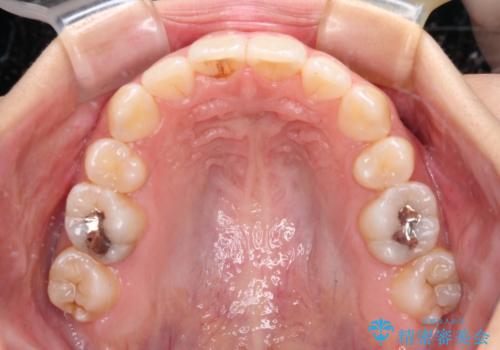

デコボコと八重歯の目立つ前歯 ワイヤー装置による抜歯矯正

奥歯の咬み合わせが理想的であり、歯の移動に時間のかかる出っ歯でもなかったため、2年程度で治療を終えることを目標としましたが、無事に予定通りの2年間で終えることができました。